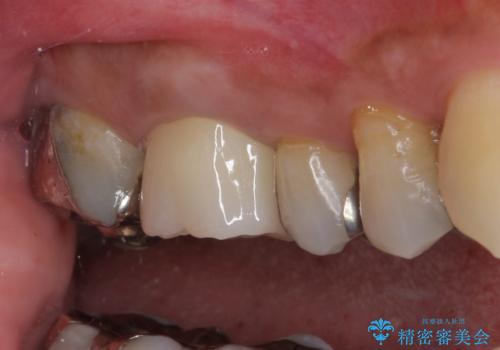

- 右上の小臼歯部に咬んだときに強い痛みを感じるとのことで来院された患者様です。

診査を行った結果、根管治療を行った後にオールセラミッククラウンにて補綴する治療計画となりました。

咬んだときの痛みに加えて夜間のズキズキする痛みもありましたが、1回目の根管治療実施後間もなく咬んだときの痛みがなくなったので、2回目に根管充填を行いました。